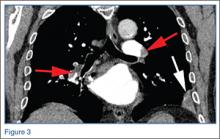

The frontal chest radiograph demonstrated abnormal peripheral opacity at the left lung base (white arrow, Figure 1b), and the noncontrast chest CT demonstrated a peripheral, wedge/pyramid-shaped subpleural ground-glass opacity (white arrow, Figure 2b). Based on the persistent peripheral opacity despite treatment, and the patient’s clinical symptoms of acute sharp chest pain/hemoptysis, a pulmonary infarct was considered as part of the differential diagnosis, and a contrast-enhanced pulmonary embolism (PE) protocol CT was obtained for further evaluation. A coronal image from the contrast-enhanced CT demonstrated the wedge-shaped peripheral opacity (white arrow, Figure 3) as well as filling defects in the bilateral pulmonary arteries (red arrows, Figure 3), indicating the presence of PE.

Large PE, such as those seen in this case, may result in peripheral infarcts due to occlusion of the pulmonary arteries. The subpleural location of the infarcts typically causes acute pleuritic chest pain, which this patient experienced.